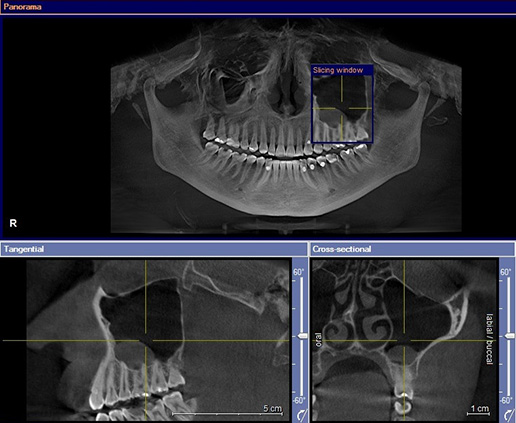

The application of thermography of diagnostic of chronic odontogenic inflammations – a case report Streszczenie Pod koniec XX wieku w diagnostyce lekarsko- -stomatologicznej zaobserwowano wzrost zainteresowania metodami termograficznymi. O ile piśmiennictwo obejmujące przydatność tej metody w diagnostyce guzów nowotworowych, stanów zapalnych zatok obocznych nosa czy gruczołów ślinowych jest dość obszerne, o tyle publikacje dotyczące zębopochodnych ognisk…